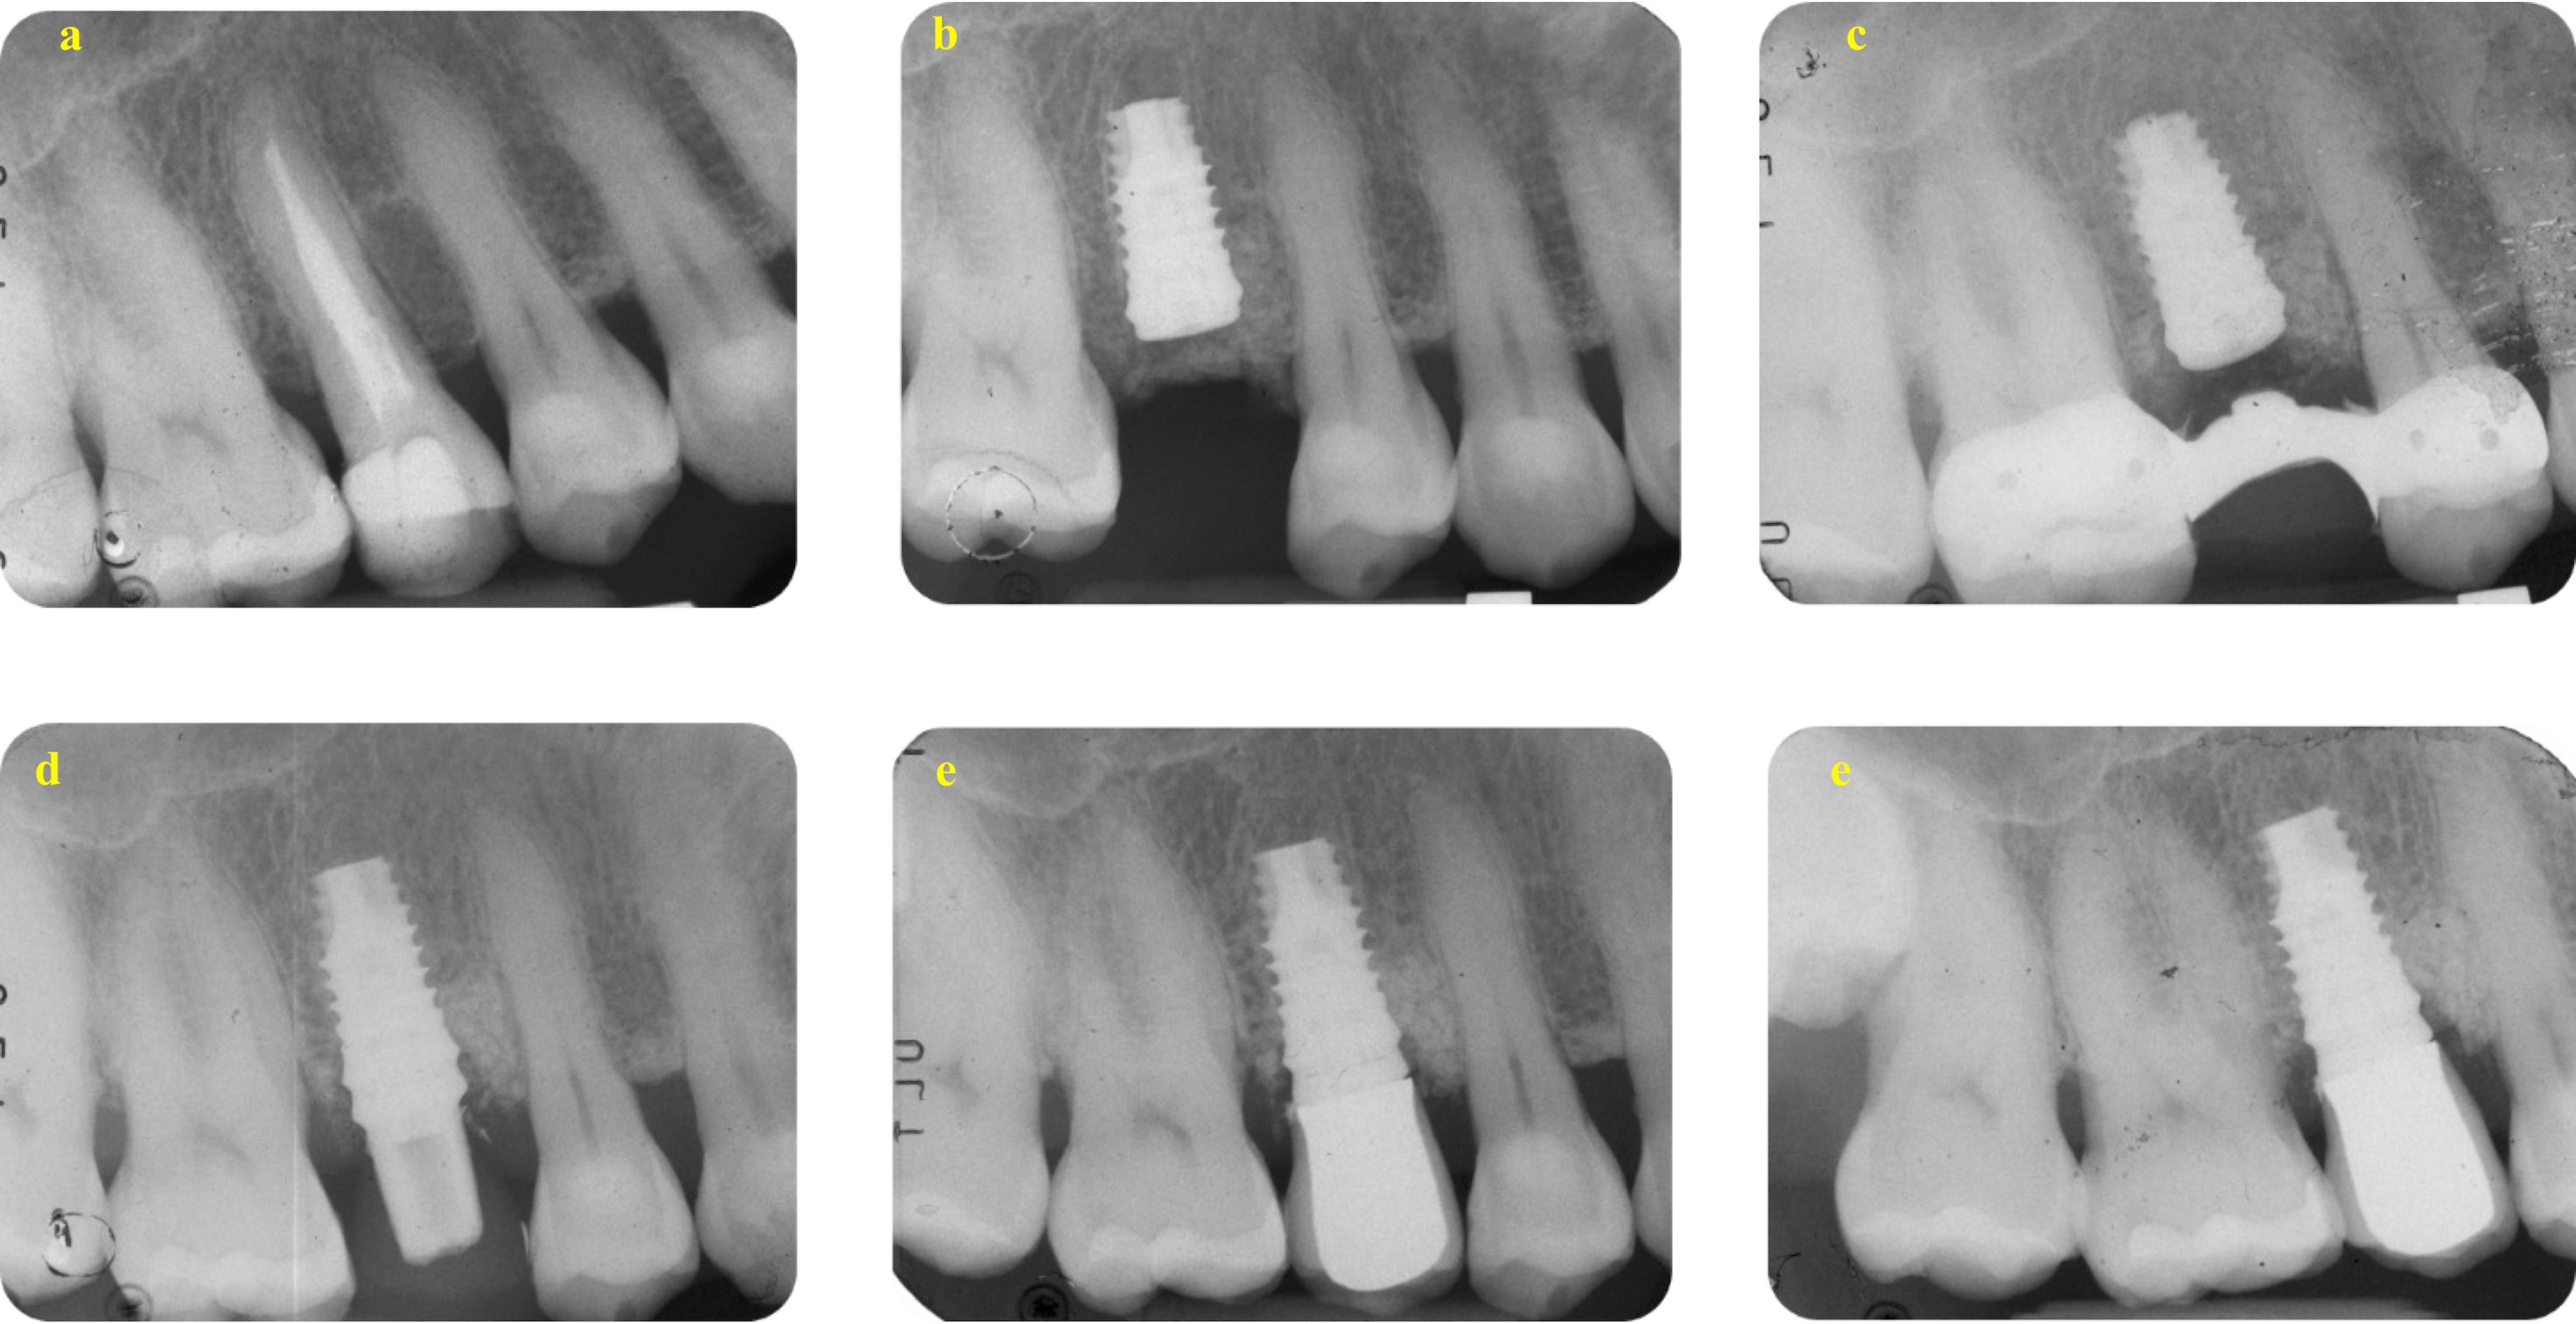

The distribution of MBL classes is presented in Table 7. Among the 56 implants, mean MBL at four years was 0.95 mm (95% CI 0.82 to 1.09) and 1.25 mm at eight years (95% CI 1.09 to 1.40), respectively, with a statistically significant MBL increase of 0.29 mm (95% CI 0.19 to 0.40, P-value < 0.001). Representative cases of teeth included in the study with an 8-year follow-up are shown in Figs. 4 and 5.

Fig. 4

A representative case on the Endo group. (a) The DM-Score was + 1 and suggested a root canal retreatment. Score was calculated as follows: no residual walls (-8), no deep carious lesion (+ 2), CEJ MBL distance was less than 3 mm (+ 3), initial PAI was 3 (+ 2) and no preoperative post was present (+ 2). (b) Root canal obturation was made using a carrier-based technique associated to an epoxy-resin based sealer. (c) post endodontic reconstruction was performed after 14 days from filling. (d) A carbon post was inserted and tooth was prepared to receive a provisional crown that was maintained up to 6 months. (e) After 6 months, a definitive crown was cemented. (f) After 8 years, periapical tissues are stable and healthy, with no modifications